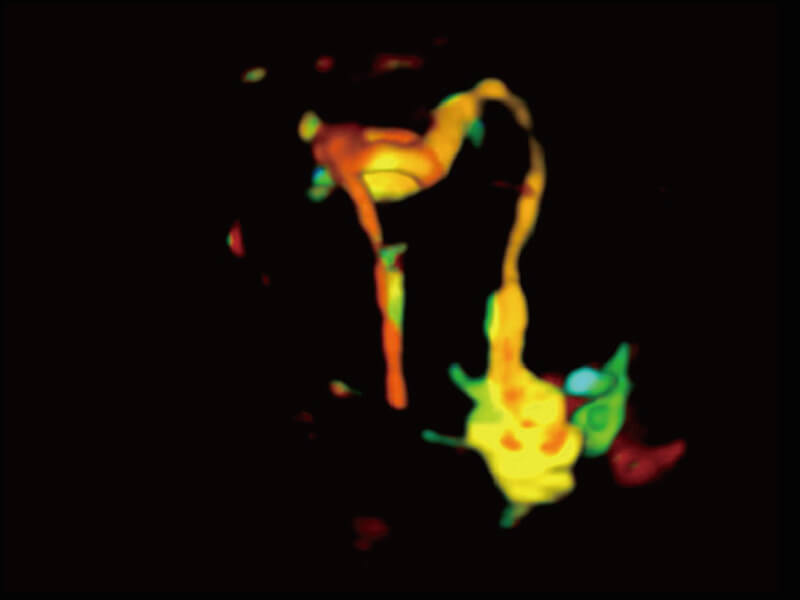

高分辨率容积成像 栩栩如生

超宽频带技术,为容积成像带来优质的二维图像基础,为您呈现丰富的结构细节,栩栩如生地展示宝宝的宫内形态以及各种组织的立体结构。